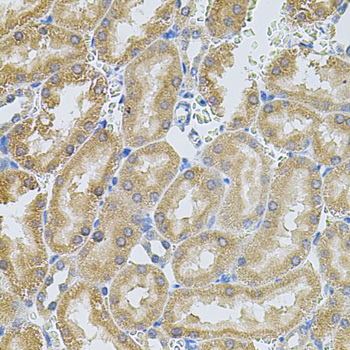

Immunohistochemistry of paraffin-embedded rat kidney using MMP10 antibody at dilution of 1:100 (40x lens).